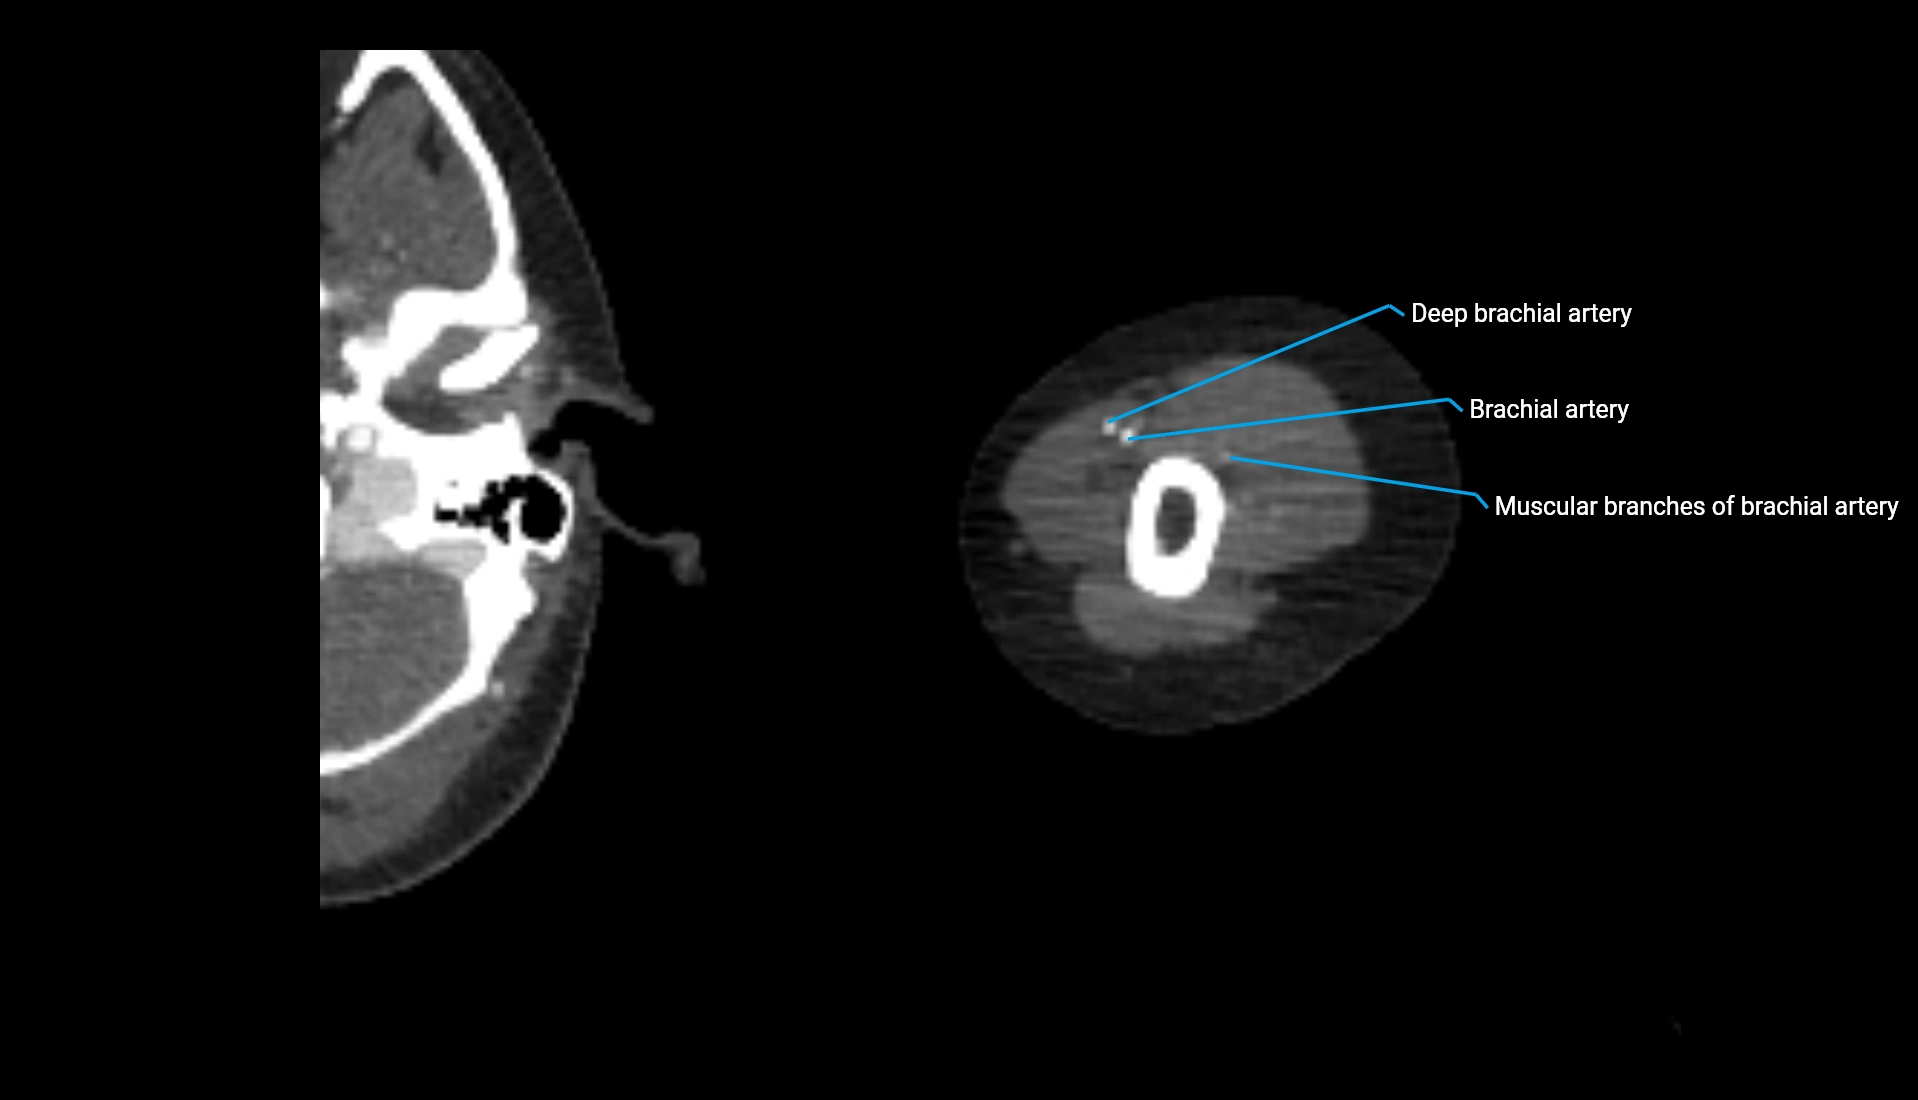

CT Appearance

Non-Contrast CT:

• Cortex: High-density, sharply defined

• Subchondral bone: Dense cancellous matrix

• Articular surface: Smooth concave contour articulating with the capitellum

• Excellent for evaluating bone integrity, alignment, and subtle fractures